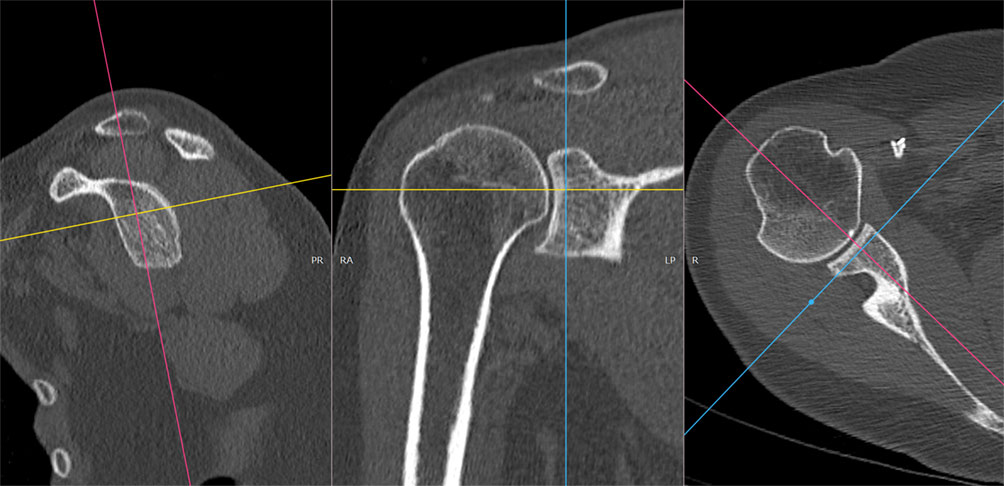

Aspect de reformatare în 3 direcții ale spațiului, reconstrucție MPR

În funcție de cerința medicului radiolog, după aceste reconstrucții multiplanare (MPR), operatorul ar trebui să realizeze secvențe MPR groase, în care prin însumarea planurilor să se poate urmări mai ușor o anumită structură, de exemplu un traiect de fractură.

Image

Aspect de reformatare în 3 direcții ale spațiului, recontrucție MPR gros

În anumite cazuri, reconstrucțiile de tip MIP (maximum intensity projection) pot fi utile (mai ales în situațiile în care se dorește măsurarea de unghiuri/axe biomecanice)

Aspect de reformatare în 3 direcții ale spațiului, recontrucție MIP